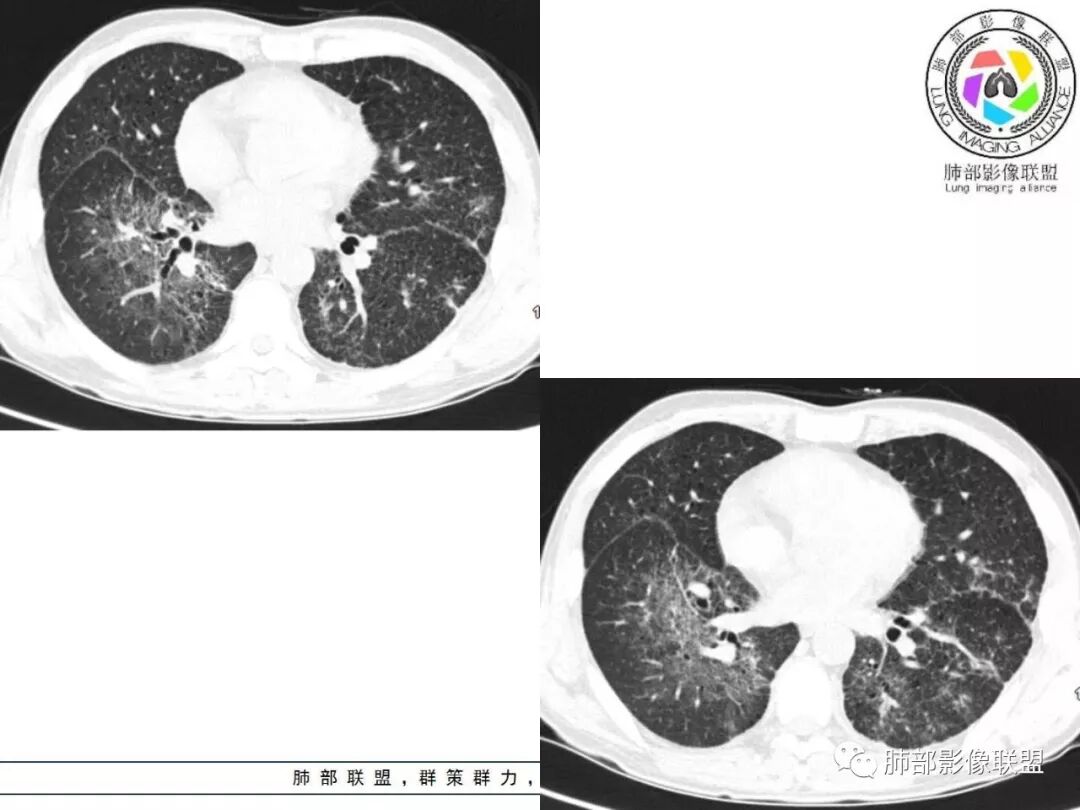

双肺间质性病变,中央间质增厚,胸膜下间质增厚,左侧胸膜肥厚,胸廓变小,肋间隙变窄。

对,大的支气管血管周围

胸部CT:两肺弥漫病灶,磨玻璃影,少许实变,部分累及胸膜,磨玻璃区可见囊?少许胸腔积液,两肺可见结节,支气管血管束增粗,小叶间隔增厚,支气管走形有扭曲扩张,可见纤维化。气肿、大泡。考虑:感染性病变,PCP?查下HIV,CD4,G等。鉴别结核、结缔组织病肺浸润。

患者中年男性,发热1月,体温38℃-39℃,峰值40℃,无畏寒、寒战,伴黄痰,CRP升高明显,降钙素原稍升高,血沉、血糖正常。胸部CT:两肺弥漫病变,磨玻璃影+点片渗出,部分累及胸膜,磨玻璃区边界清楚,少许胸腔积液,两肺支气管血管束增粗,小叶间隔增厚,部分支气管走形有扭曲扩张,可见肺气肿、右肺尖肺大泡及部分纤维化改变。综合考虑:感染性病变。结核或PCP可能性大,鉴别风湿免疫、结缔组织疾病肺浸润和腺癌等恶性病变。

胸部CT:两肺弥漫病灶,中央间质分布为主,部分位于胸膜及叶间裂旁,磨玻璃影,斑片影,部分实性结节,肺气囊,支气管血管束增粗,小叶间隔增厚,叶间裂不均匀增厚,支气管走形有扭曲扩张,可见纤维化、气肿、大泡。考虑:LIP加MALT。鉴别PLCH、PCP、结核、结缔组织病肺浸润。

双肺弥漫性病变,多发磨玻璃密度及小叶间隔增厚,大部分沿支气管血管束分布,伴支气管轻度扩张,以午后及晚上发热为主,考虑感染性病变,间质性结核可能大,另双肺多发肺气囊,LIP待排

病灶呈片状磨玻璃密度影,呈典型的烟花征。磨玻璃影密度偏高,有网结节样改变,与正常肺实质分界清楚,且常见相对高密度的勾画。

烟花征分为3肿类型:晕征、反晕征及均匀分布。

病变一般沿血管支气管束分布或小叶分布,一般上肺多于下肺(这与常见继发性肺结核分布相若)。

常会伴有其他继发性肺结核病灶,如斑片影、结节影,树芽征,新旧不等改变。

2. 肺气肿背景(小叶中心性肺气肿);双肺多发病灶整体沿血管支气管束及胸膜下分布,以上叶及下叶背段分布为主,有实变及GGO,边界清楚,有树芽,小叶间隔及中央间质增厚,叶间裂见到多发结节,部分支气管不规则牵拉扩张,提示病灶纤维化明显,结合临床病史,考虑病灶为间质性感染,肺门及纵隔内有钙化淋巴结,小叶间隔结节,考虑淋巴道增值性疾病可能,综合常规要怀疑间质性肺结核。